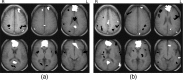

Several brain areas show signal decreases during many different cognitive tasks in functional imaging studies, including the posterior cingulate cortex (PCC) and a medial frontal region incorporating portions of the medial frontal gyrus and ventral anterior cingulate cortex (MFG/vACC). It has been suggested that these areas are components in a default mode network that is engaged during rest and disengaged during cognitive tasks. This study investigated the functional connectivity between the PCC and MFG/vACC during a working memory task and at rest by examining temporal correlations in magnetic resonance signal levels between the regions. The two regions were functionally connected in both conditions. In addition, performance on the working memory task was positively correlated with the strength of this functional connection not only during the working memory task, but also at rest. Thus, it appears these regions are components of a network that may facilitate or monitor cognitive performance, rather than becoming disengaged during cognitive tasks. In addition, these data raise the possibility that the individual differences in coupling strength between these two regions at rest predict differences in cognitive abilities important for this working memory task.